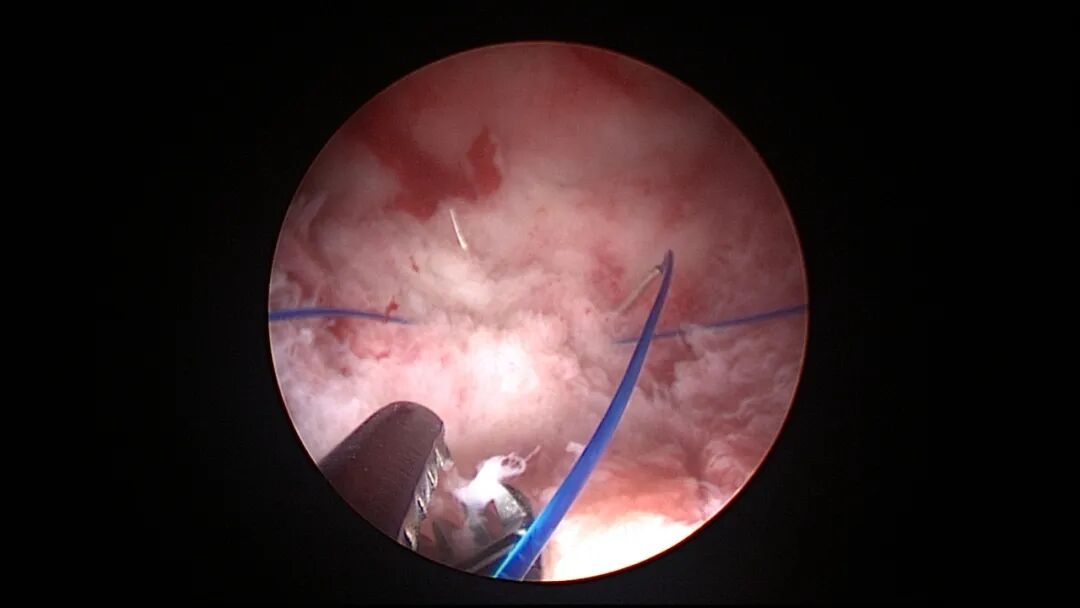

操作步骤描述:宫腔检查镜可完成操作,扩张宫颈至7号扩宫棒,检查镜能轻松通过,避免镜鞘与节育环纵臂在宫颈管形成卡压及筷子效应,影响操作,或卡压摩擦阻力大带出节育环。可用单级电针在宫底扎出小凹坑做标记或作为置入挂钩的隧道(不是必须的)。将挂钩用异物钳直视下送入宫腔,或用中弯钳盲视下送入宫腔,异物钳夹持挂钩将倒钩端插入宫底肌层,越过倒钩。用环尾丝或不可吸收线在节育环顶端打结,形成一个线圈,直径约0.5cm~1cm,结打在线圈旁边,便于夹持操作。将环装回推杆送入宫腔,再夹住节育环固定线圈抵紧宫壁稍旋转就可以将线圈滑进挂钩缺口,挂到挂钩上,可再次向宫底推送挂钩少许,不必夹闭挂钩缺口,重力作用和内膜生长都会阻止线圈脱出,可以用电针电凝挂钩周围组织,进一步防止挂钩脱落。异物钳原位固定节育环,退出宫腔镜,距宫颈外口0.5cm~1cm剪断剩余尾丝。宫颈扩张到9号扩宫棒,冷刀系统异物钳夹持挂钩及线圈也可完成以上操作。

单级电针标记挂钩位置

取胚术后丝线挂钩固定节育环图片及视频

子宫腺肌症内膜息肉切除后丝线挂钩固定曼月乐并电凝图片及视频

异常子宫出血内膜增生节育环尾丝挂钩固定曼月乐图片及视频